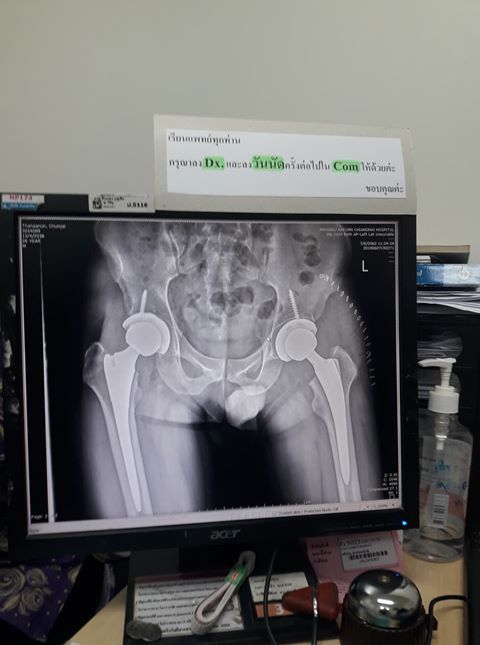

หัวกระดูกสะโพกตาย จากการที่ รับประทานยากลุ่ม สเตียร์รอยด์ในการรักษาโรค SLE สุดท้ายต้องผ่าเปลี่ยนข้อสะโพกทั้งสองข้าง และไม่สามารถวิ่งได้อีกตลอดชีวิต

กว่าหมอจะบอกผมว่าไม่ควรทำ ก็สายไปแล้ว สุดท้ายไม่ได้จบแค่ SLE ต้องผ่าตัดสะโพกอีกสองข้าง ต้องวิ่งไม่ได้อีกตลอดชีวิต